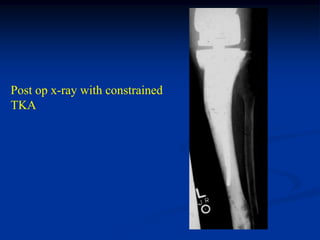

71 year female with Ollier’s left lower extremity

Lateral view of knee

Photomic

Failure following

resurfacing TKA

because of loosening

Post op x-ray with constrained

TKA

X-ray of cemented

stem distal femoral

resection prosthesis